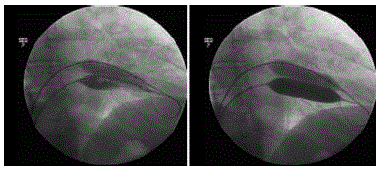

Abaixo estão reproduzidas imagens de valvoplastia mitral percutânea (VMP) para serem analisadas.

Assinale a assertiva que NÃO se correlaciona com a técnica utilizada.